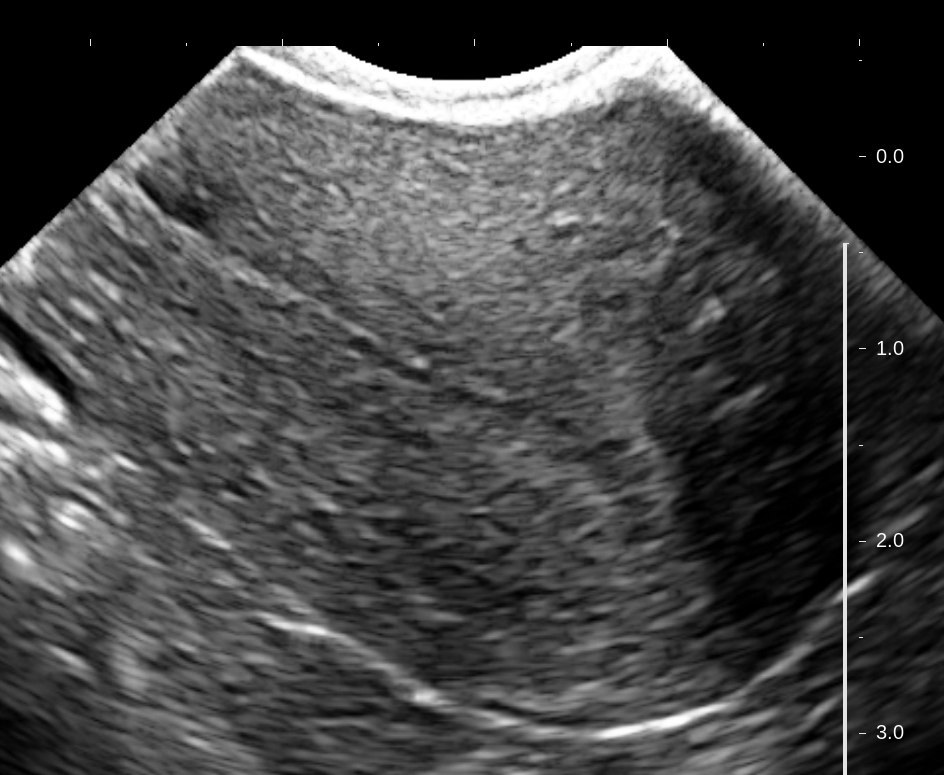

Медицинская диагностика: Гиперплазия эндометрия на УЗИ